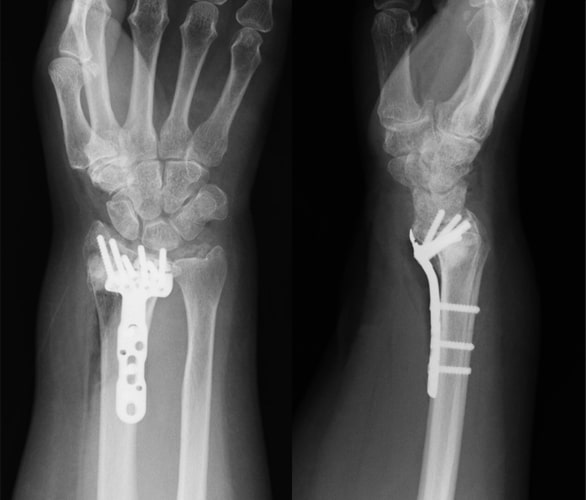

橈骨遠位端骨折

橈骨遠位端骨折写真

術前

橈骨遠位端骨折術後写真

ロッキングプレート固定術後

原因

踏み台やベッドから転倒した際に、手をついて受傷することが多いです。

症状

手首の関節部の痛み、腫れ、変形などが生じます。X線で橈骨(前腕の親指側の骨)の遠位部分に骨折を認めます。大きくズレている場合は手指のしびれが生じることもあります。

治療方針

ほとんどズレがない場合はギプス固定をして治す場合もあります。しかしギプスをしていてもズレてくる危険性が高い場合や関節面がズレている場合は手術が必要となります。手術は専用のプレートを用いて行うことが多いです。